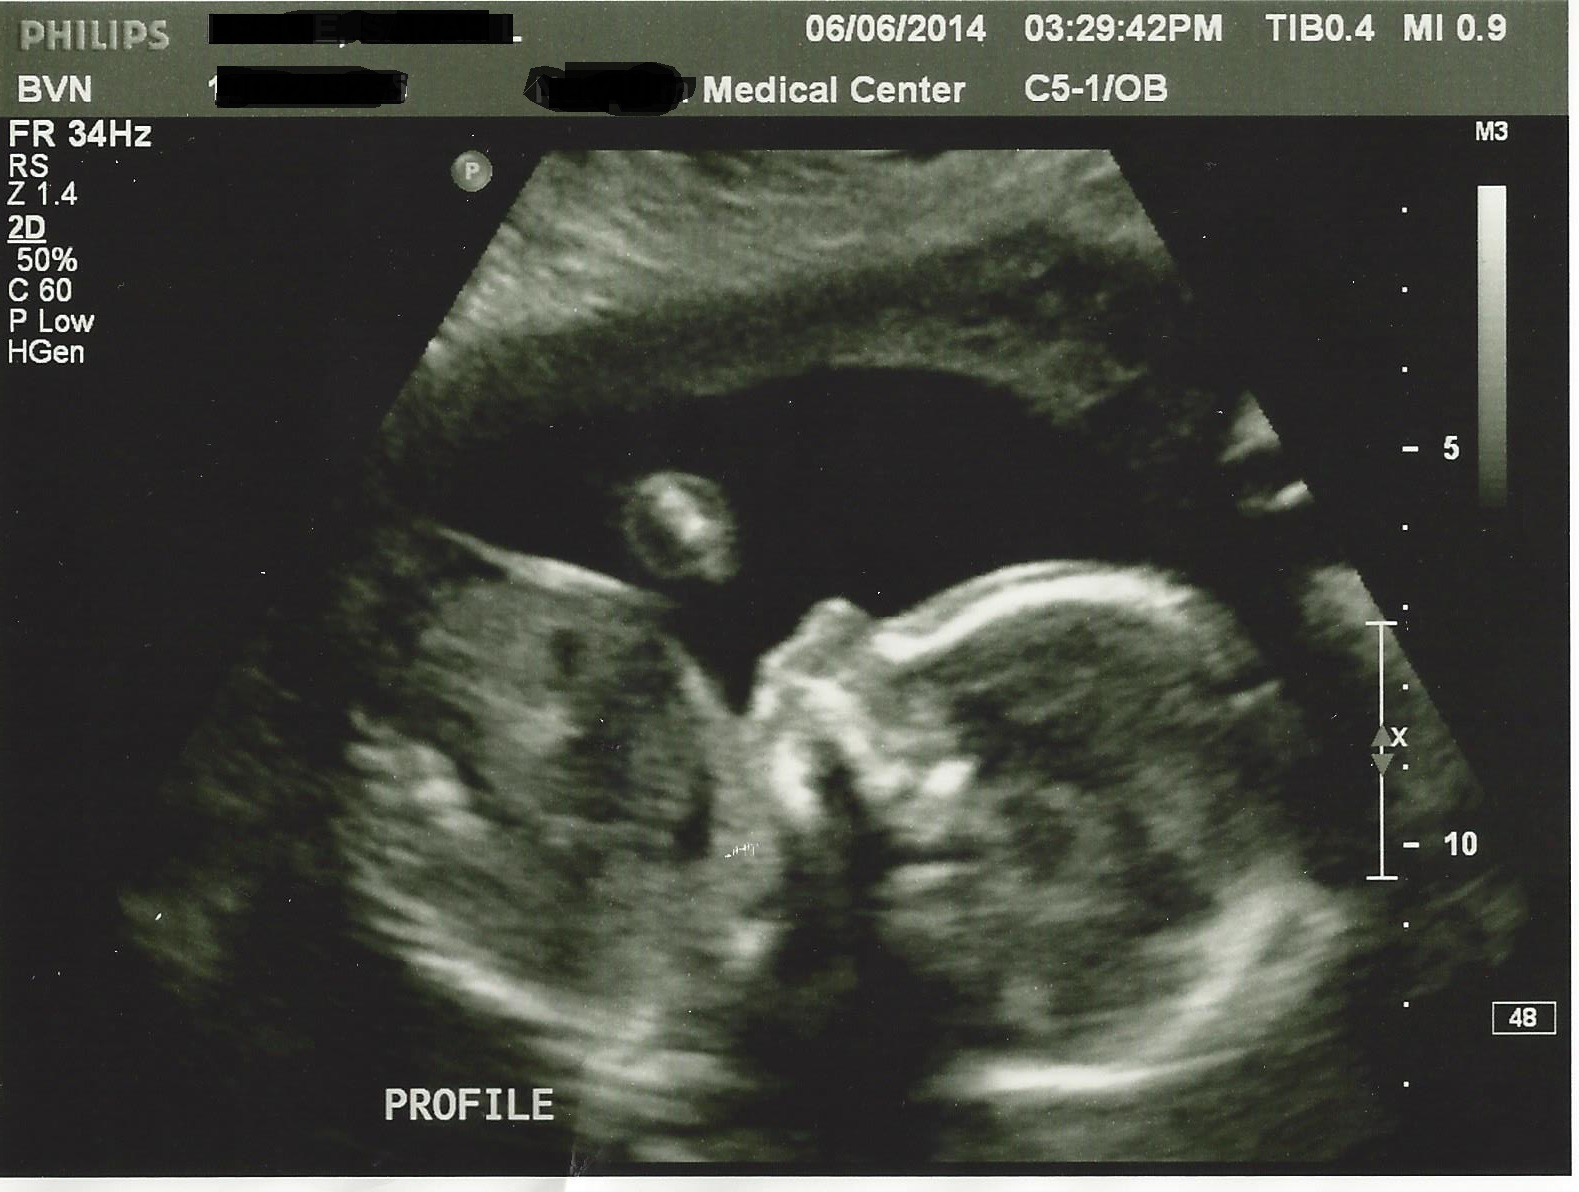

a baby! Still Team Green

Finally got my chance for the 20 week anatomy scan yesterday. Everything looked great and baby was very active making it difficult to get a good profile shot. HB was going crazy and s/he was making little sucking movements, so cute! I still can't believe that's a person in there even though we've been through this before, it's no less surreal.

As I suspected, baby is measuring 1-2 weeks ahead and according to the average measurements my EDD is 10/13 vs. 10/22. I know I ovulated early (or else I wouldn't have been pregnant this soon - but am thrilled!). OB won't change my due date but I won't be surprised if I go earlier than 10/22.

So here's baby L!